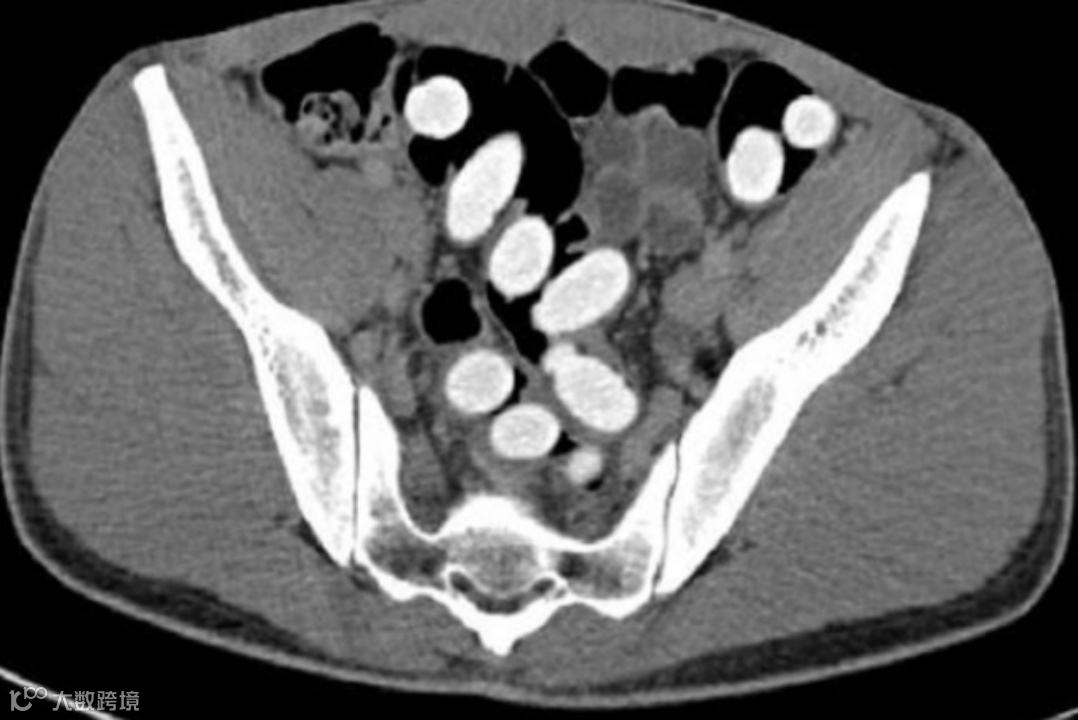

作为普通的放射科医生或技师,我们也可以在反诈、禁毒中尽自己的绵薄之力,尤其是看到这样图像时,请立即报警❗️❗️❗️

腹部CT扫描显示结肠(主要是降结肠、乙状结肠和直肠)有大量椭圆形高密度异物,这可不是“可爱的蚕宝宝”,而是小包分包的可卡因,大约有300-500g。